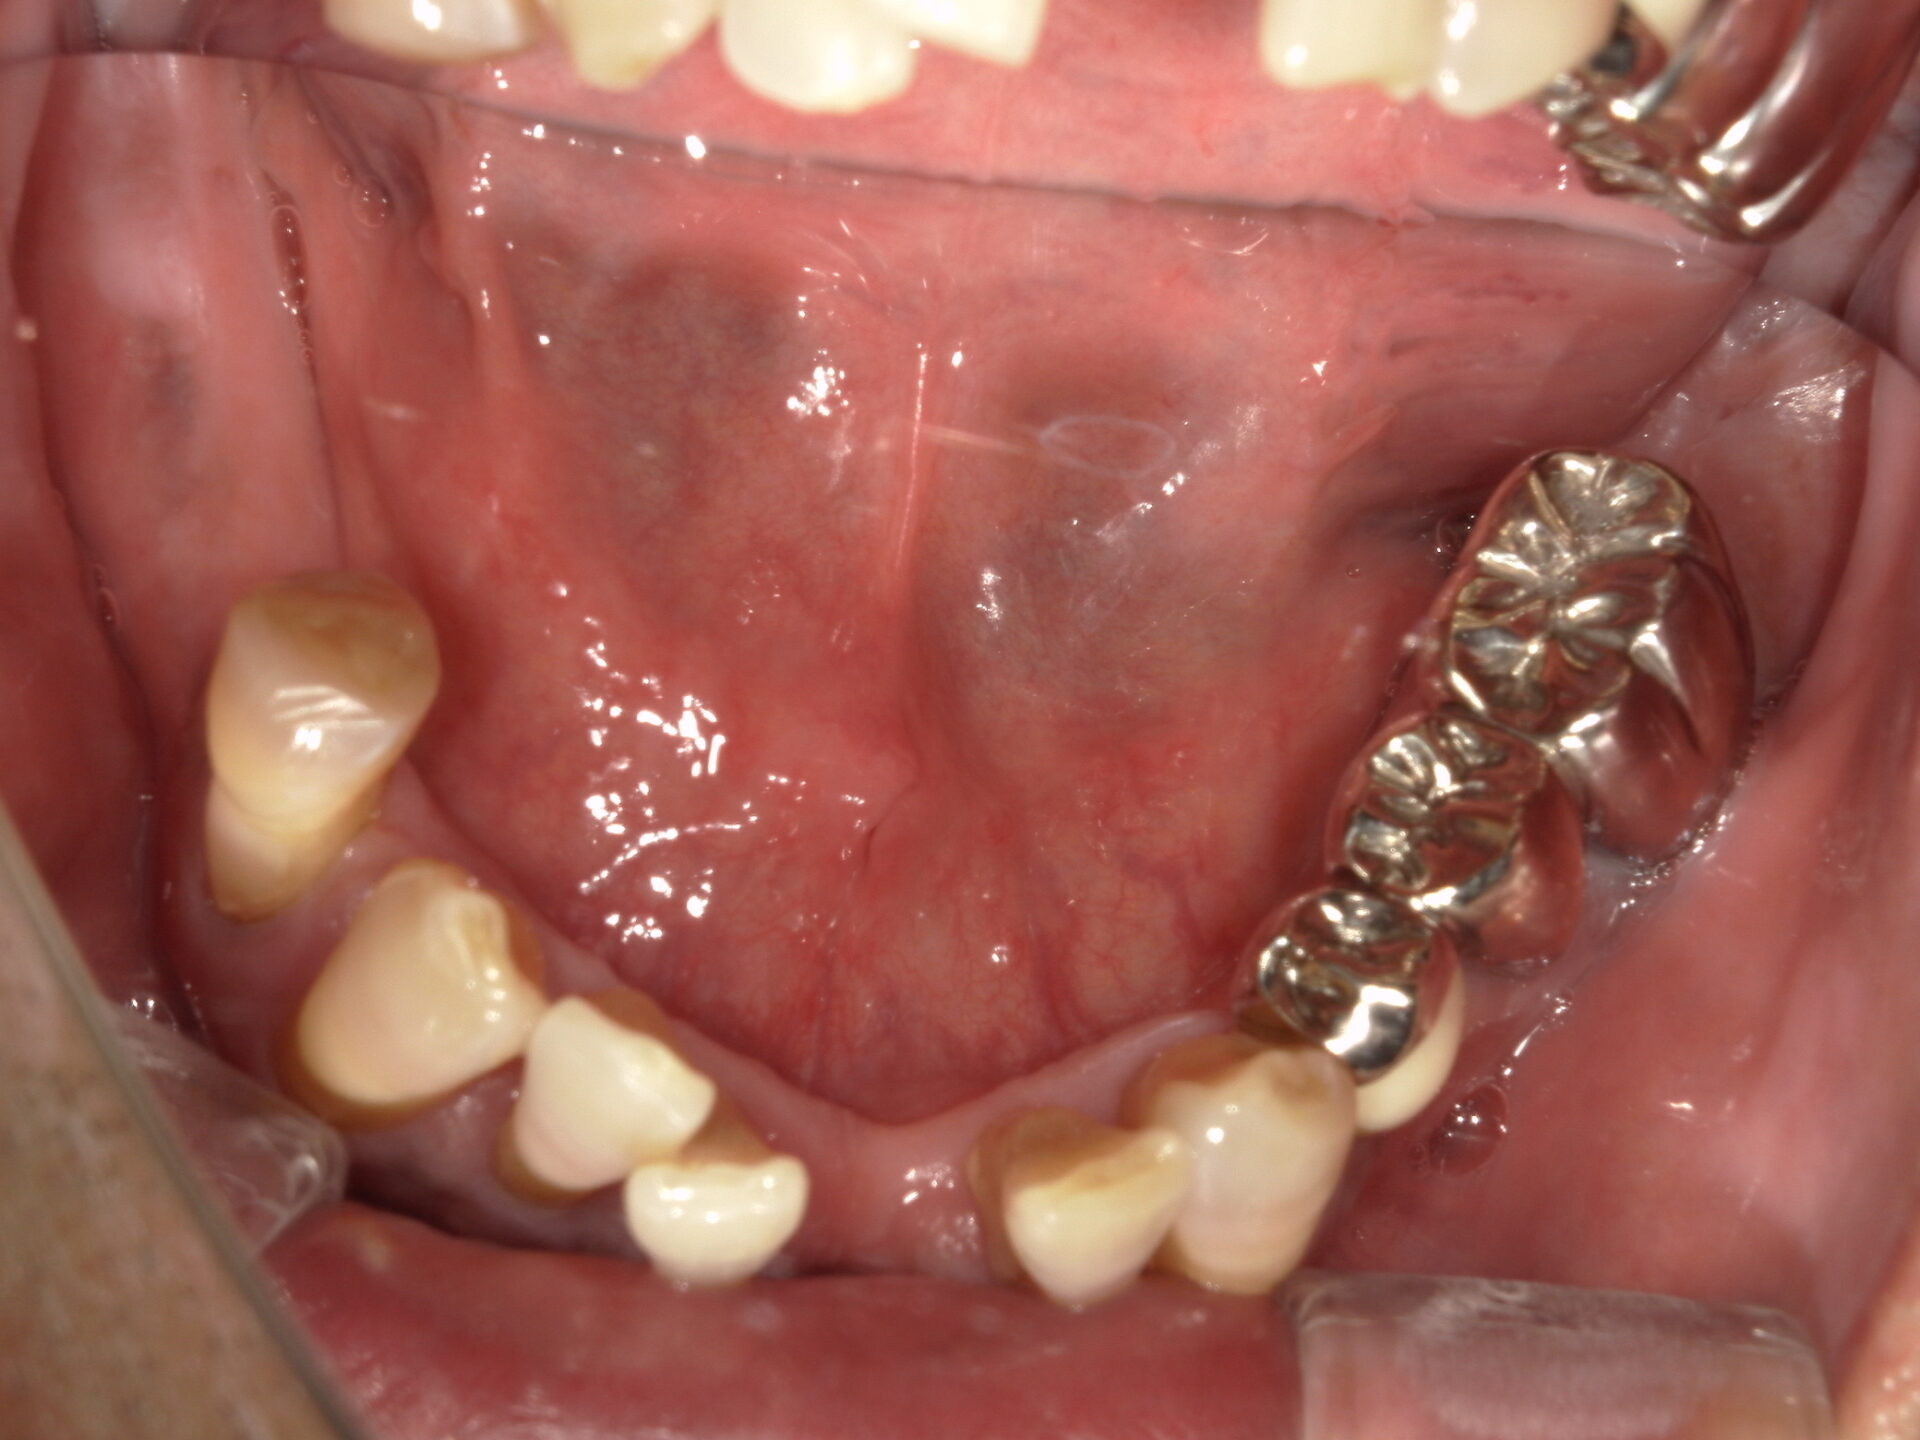

before

after

患者さんの年齢 50代 男性 症状 何も噛めない 治療内容 インプラント治療(オールオン4) 費用 費用900万(税抜) 治療期間・回数 治療期間2年・通院回数12回 メリット なんでも噛めるようになる 見た目が綺麗 デメリット・リスク 骨造成などで費用が増える場合がある - インプラント治療